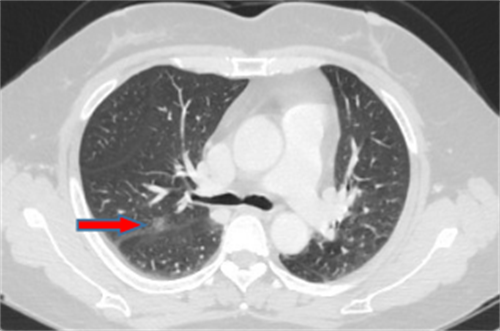

王女士,57岁,体检发现右下肺结节2月,术后病理诊断肺结节为肺隐球菌病。

李先生,45岁,发现右上肺结节2年,近期长大,术后病理诊断肺结节为炎性假瘤。

龙先生,65岁,体检发现右下肺结节,术后病理诊断肺结节为硬化性血管瘤。

郭女士,63岁,体检发现右下肺结节20天,术后病理诊断肺结节为浸润性腺癌。

王女士,65岁,体检发现右上肺磨玻璃结节16天,术后病理诊断肺结节为浸润性腺癌。

王女士,52岁,体检发现右上肺磨玻璃结节7月,术后病理诊断肺结节为原位腺癌。

王女士,35岁,新冠核酸检查阳性7天,胸部CT检查左上肺磨玻璃影,考虑新冠病毒性肺炎。